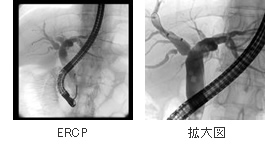

PTCD(経皮的胆管ドレナージ)やERCP(内視鏡的逆行性胆・膵管造影)という検査をします。PTCDは直接胆道に針を刺し、そこから造影剤を注入し胆嚢や胆道の描出をするものです。

黄疸の軽減や胆道の狭窄部位の検索ために行われます。

またERCPは口から内視鏡を入れ、造影剤を注入することによって胆嚢から膵管までの流れを追う検査です。